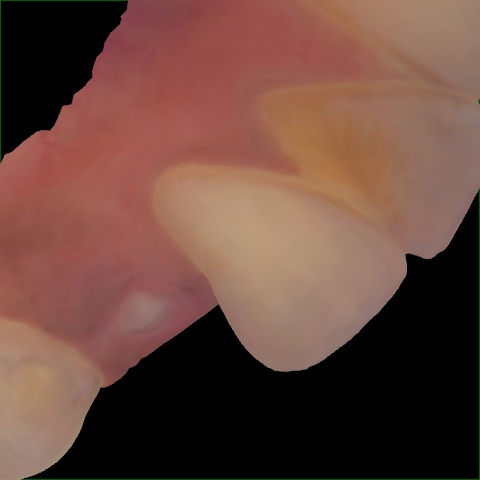

Image 160 / 400

NHD25466

Annotated as "Good"

Original Image Rendering Image